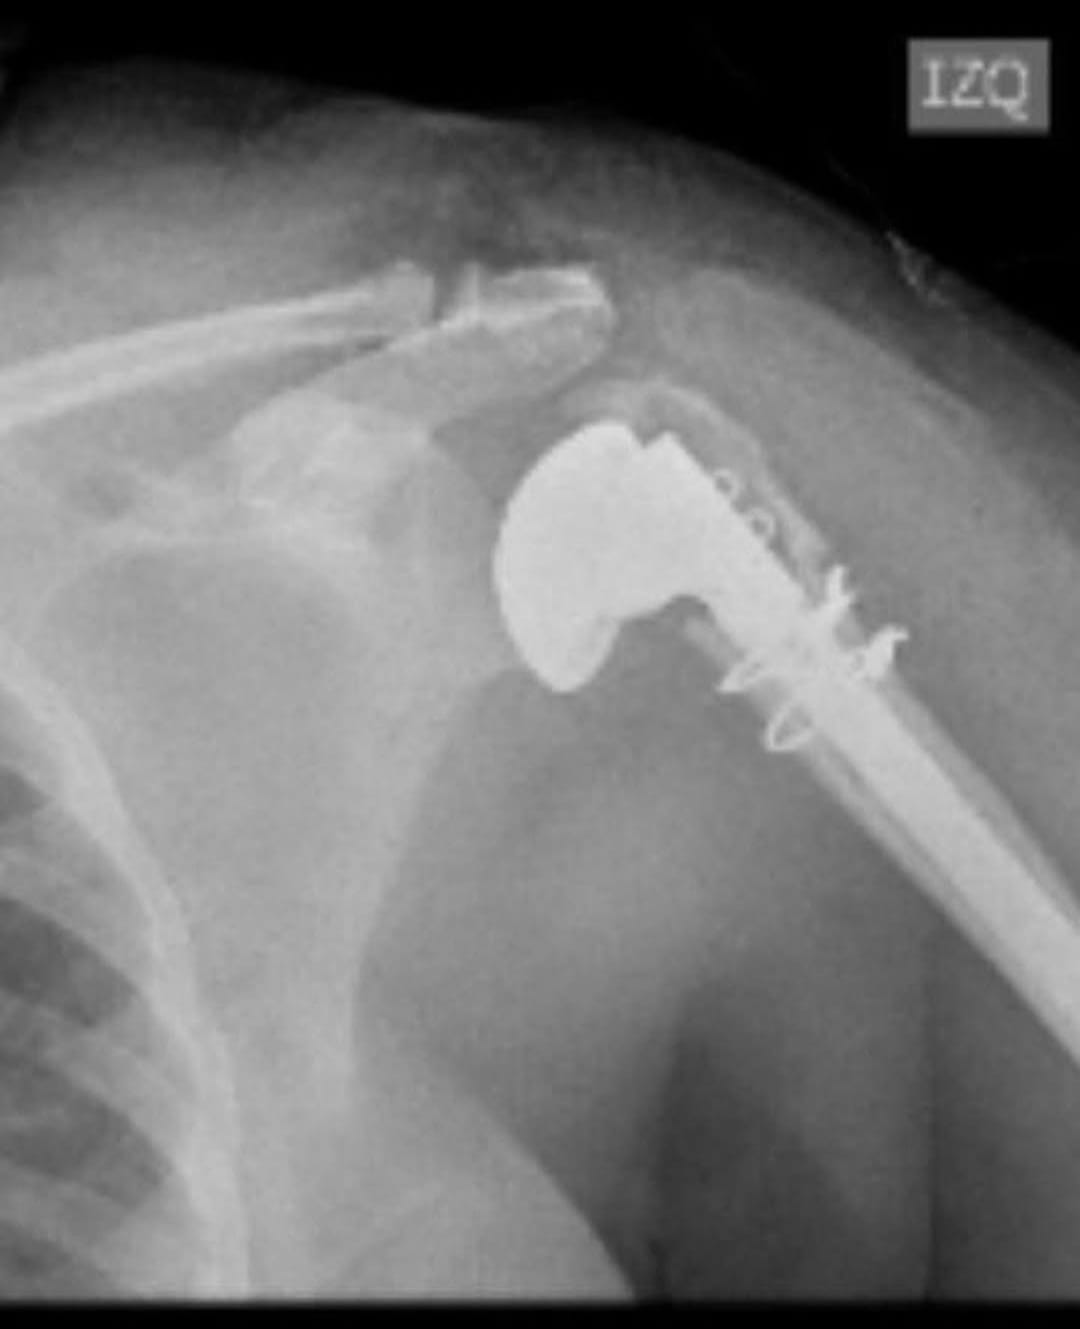

CASOS